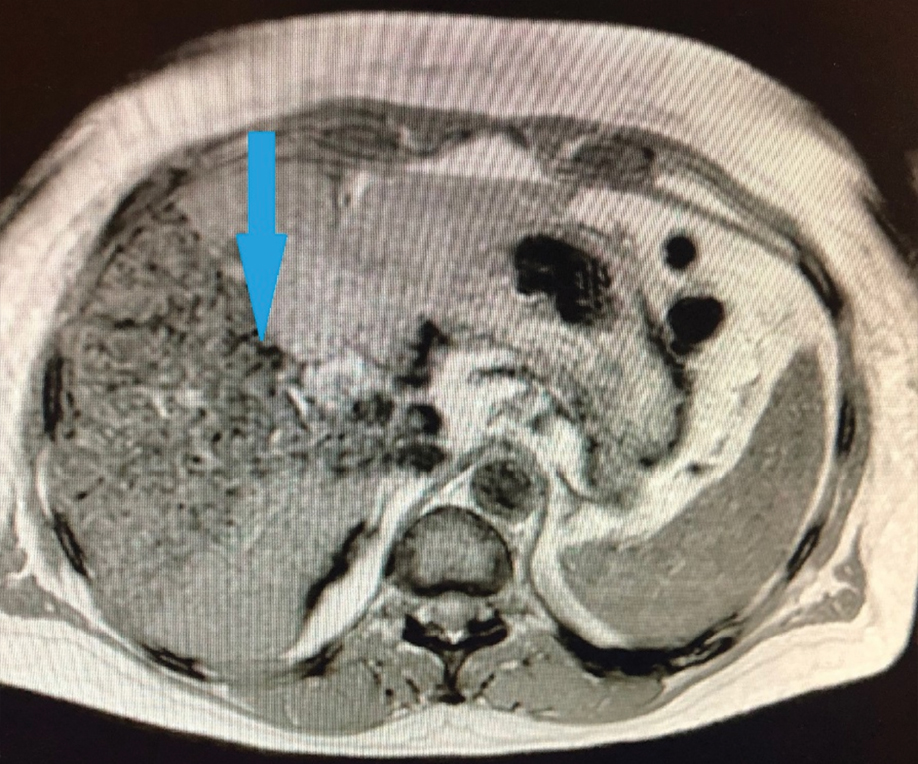

Before the injection, the culture of autologous mesenchymal stem cells was treated with iron oxide nanoparticles. During the injection, cells containing nanoparticles obtained by magnetic separation were used, which subsequently enabled visualized the stem cells injected in the patient’s body when performing magnetic resonance imaging of the abdominal organs (Figure 2). One day after the cell therapy, MRI of the abdominal cavity and chest was performed.

Рисунок 2. Магнитно-резонансная томография органов брюшной полости на 1 сутки после введения аутологичных мезенхимальных стволовых клеток в артериальное русло печени. Стрелкой указаны области печени, в которых визуализируются маркированные стволовые клетки.

Figure 2. Magnetic resonance imaging of abdominal organs on 1 day after the insertion of autologous mesenchymal stem cells into the arterial bed of the liver. The arrow indicates the areas of the liver where the marked stem cells are visualized.

In the presented MRI image of the abdominal organs, the implanted stem cells are visualized in the right lobe of the liver. Also, no cellular structures were found in any other organ of the abdominal cavity, and in the chest.